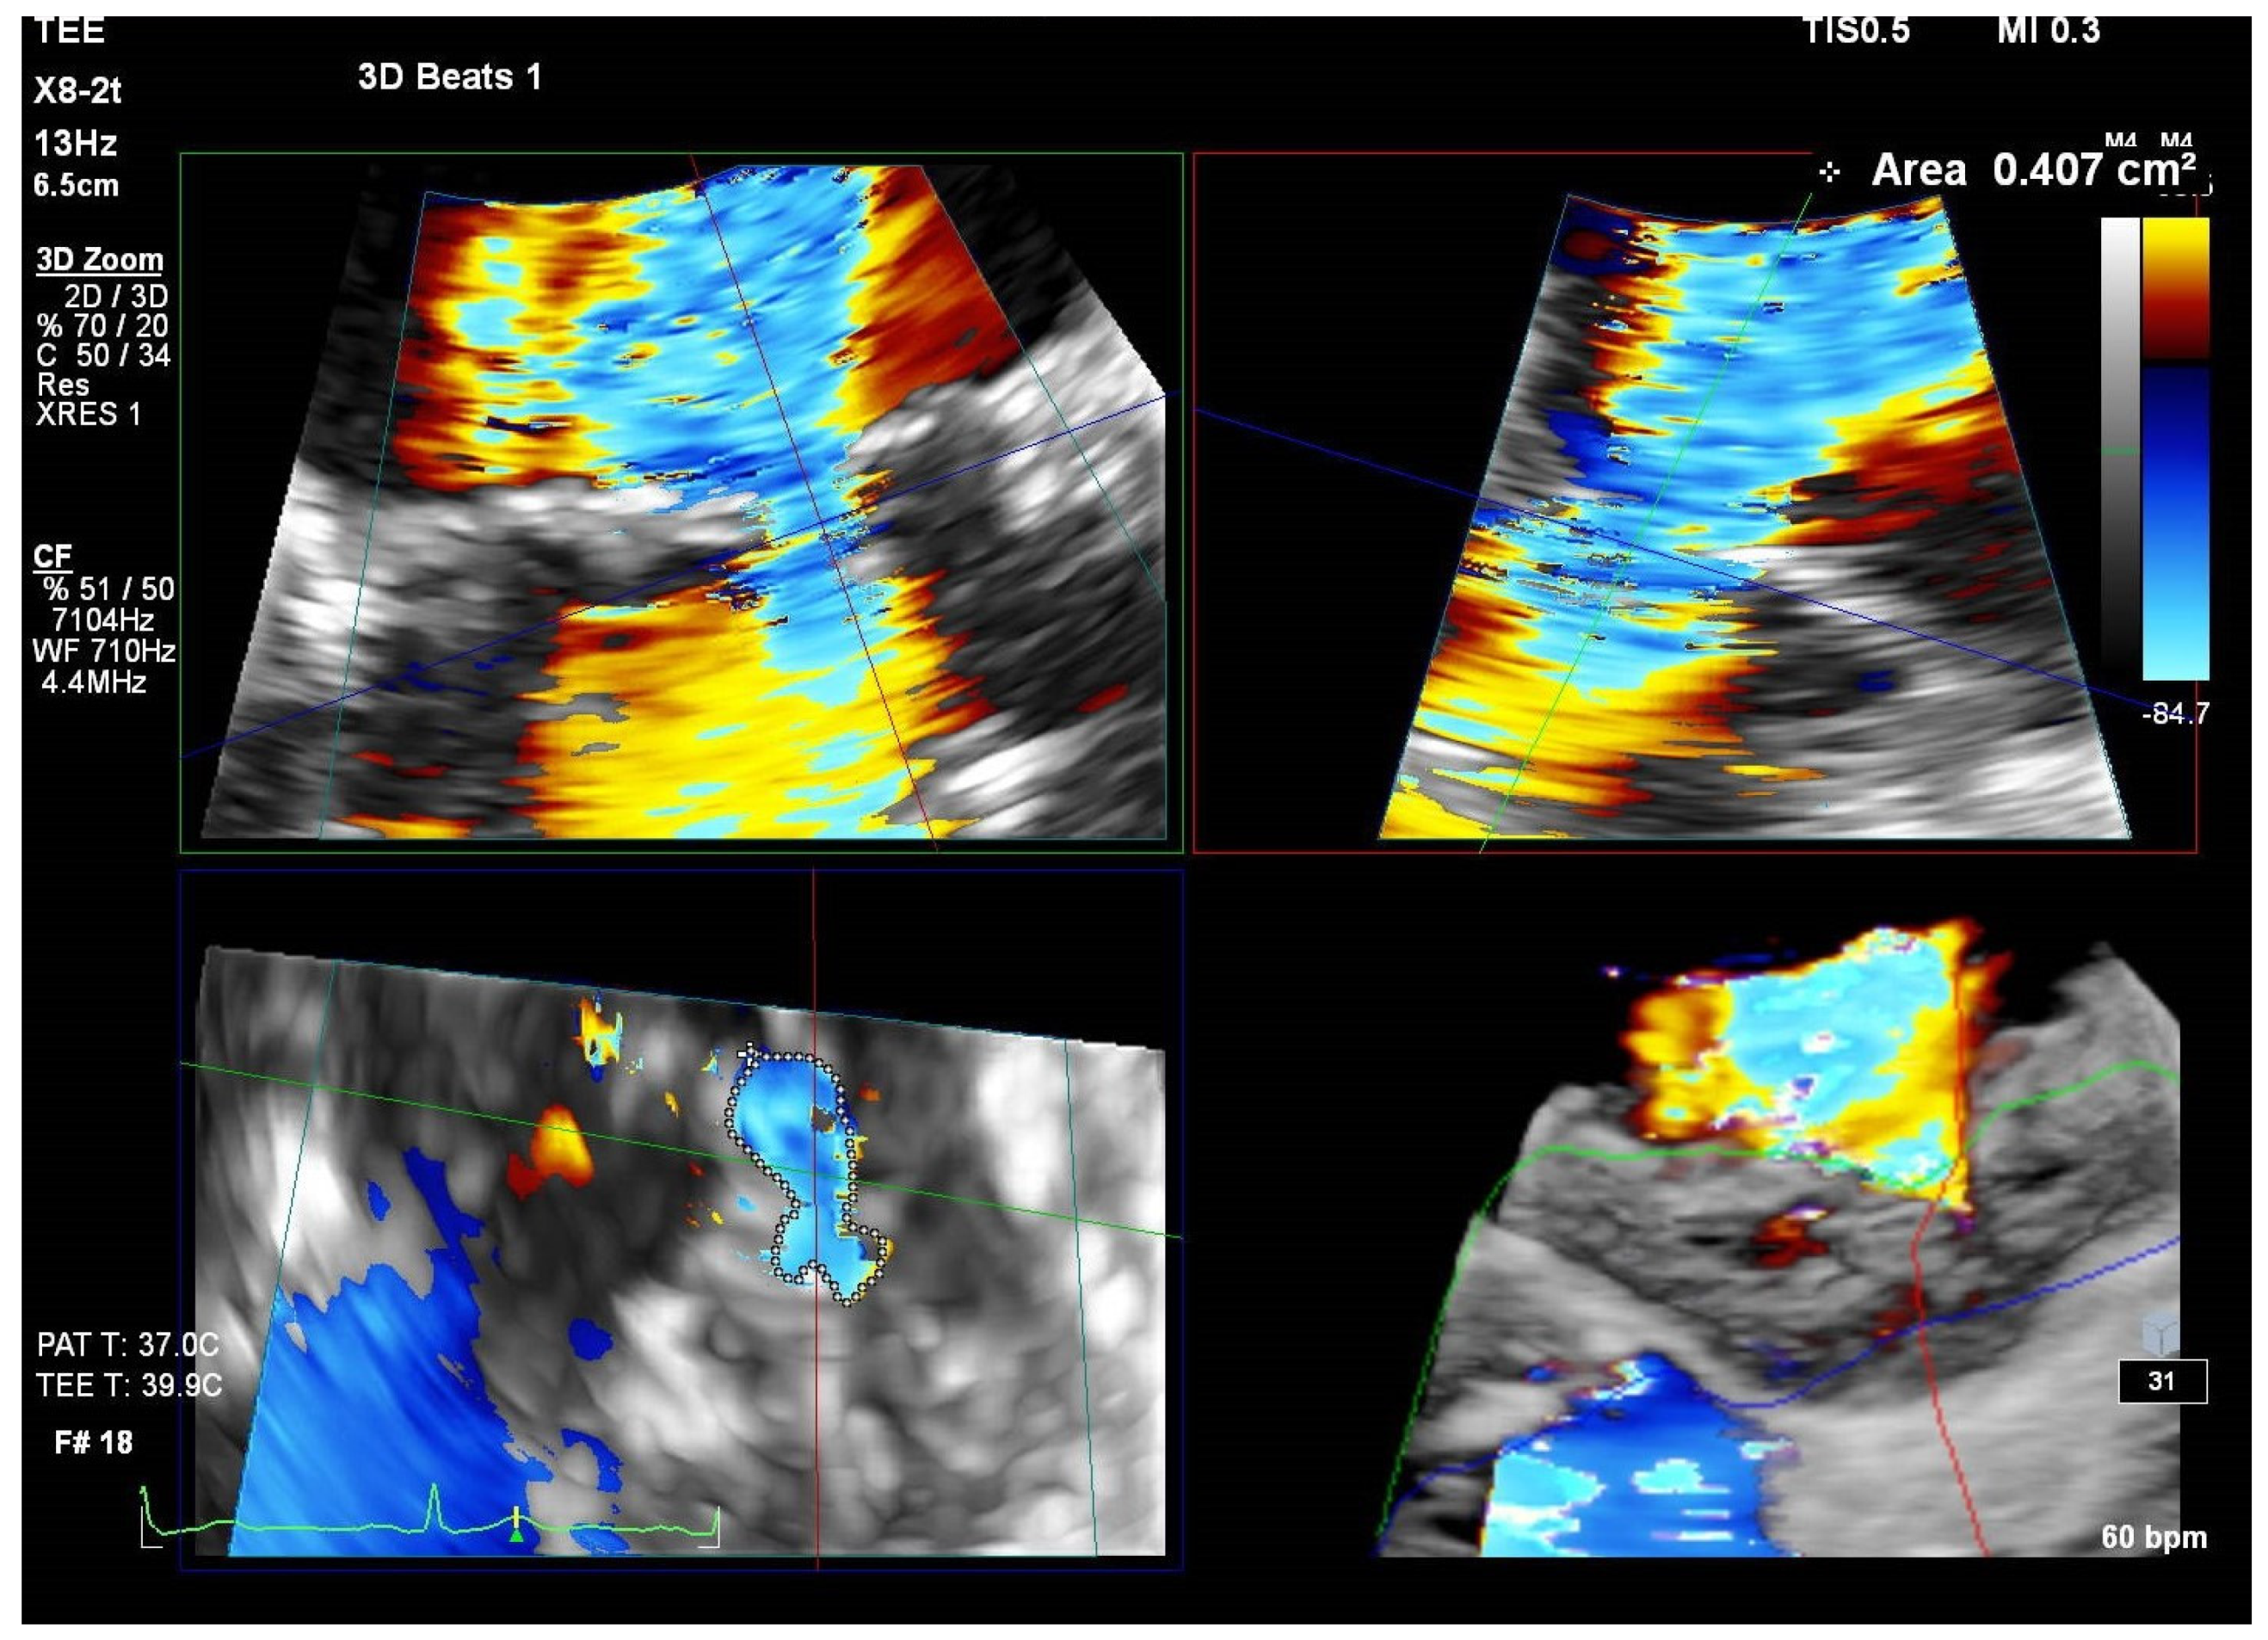

Three-dimensional echocardiography is a promising tool for the evaluation of MAC-related MR. Specifically, 3D vena contracta area obtained via TEE with 3D color Doppler provides a more accurate appraisal of MAC-related MR severity. A study by Goebel et al. [44] indicates that 3D vena contracta area (see Figure 7) correlates more closely with Rvol than the PISA method. The latter tends to overestimate EROA, leading to a potential misclassification of moderate MR as severe (see Table 2).

Figure 7.

Measurement of vena contracta area by 3D TEE. (3D TEE: three-dimensional transesophageal echocardiography).